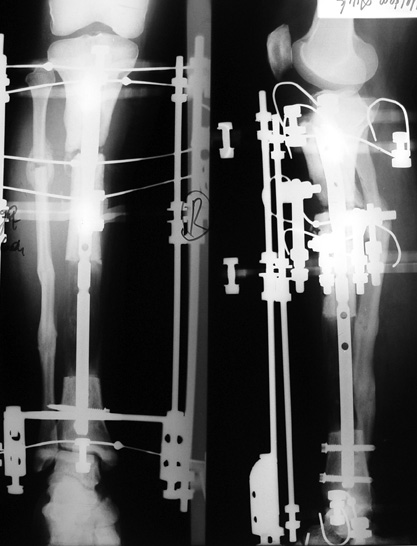

Appropriate radical debridement necessitates excision of all necrotic bone and soft tissues, and frequently causes instability at the involved extremity. The remaining bone and soft tissue defect has to be fixed and reconstructed. The distraction osteogenesis method of Ilizarov is used successfully for achievement of union, correction of the deformity, elimination of limb length inequality and reconstruction of segmental bone defects.

The duration of external fixation (external fixation index) depends on the amount of distraction required, and the extremity is prone to complications during this period. After the distraction phase is completed, the external fixator remains in place during the consolidation phase, which lasts twice as long as the distraction phase; but this period is hardly tolerated. If the external fixator is removed before sufficient consolidation is achieved, fractures, deformity and shortness will be the result. In our department, ‘lenghthening over nail’ method is used in order to decrease the external fixation index and increase patient comfort and activity level. In this method, the intramedullary nail is statically locked after the completion of the distraction phase, and external fixator is removed. The extremity is stabilized by the intramedullary nail during consolidation phase. In this way, complications due to long external fixation index or early removal of the external fixator are avoided.